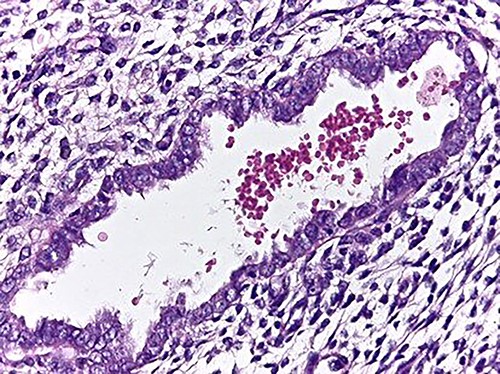

The microscopic study reported ileocolic intussusception and cecal endometriosis (Figs 4 and 5).

Low magnification image (4x); endometrial glands and stroma in the middle of the external muscular layer of the colon.